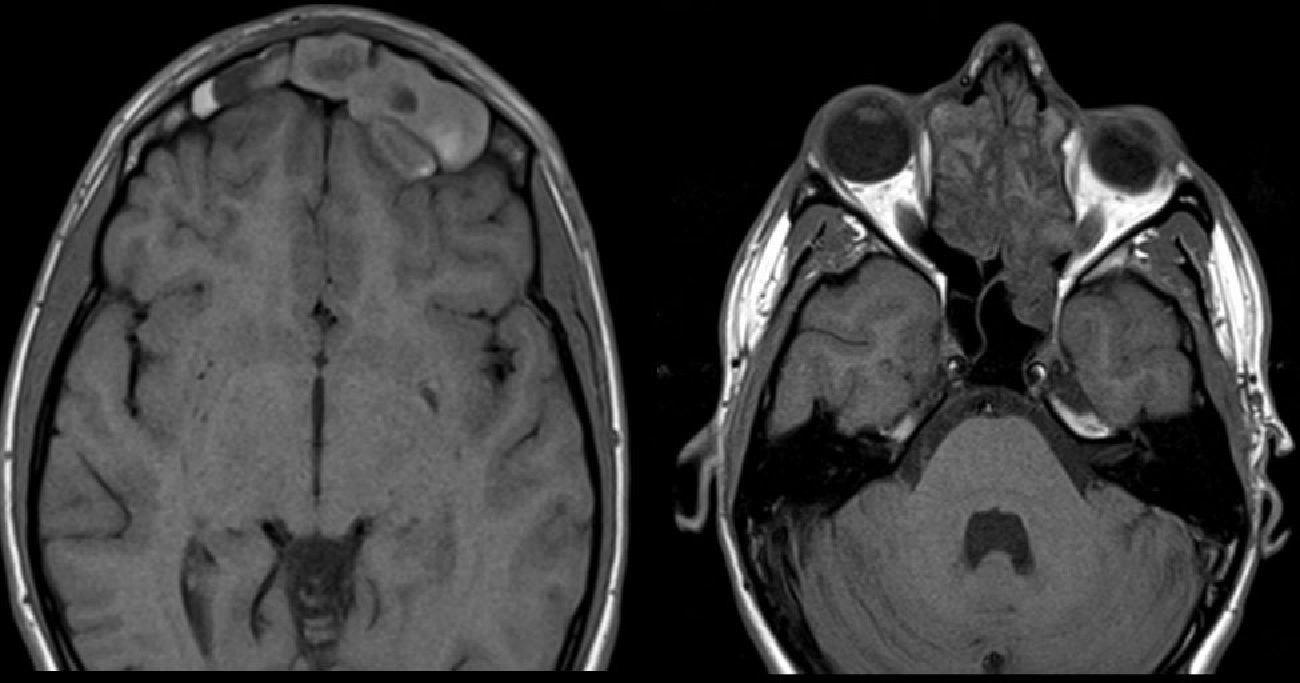

El paciente aportó un TC craneal externo donde se visualizó una extensa lesión a nivel de ambos senos fronto-etmoidales con signos sugestivos de invasión intracraneal e intraorbitaria. En vista de los hallazgos radiológicos, del tamaño de la lesión y del rápido crecimiento que refería el paciente durante el último año se decidió completar el estudio mediante una resonancia magnética (RM) que mostró una lesión isodensa en ambos senos frontales y en el receso fronto-etmoidal izquierdo que provocaba la lisis tanto de la tabla externa del hueso frontal, protruyendo hacia el tejido celular subcutáneo, como de la tabla interna, ejerciendo efecto masa sobre el parénquima frontal subyacente, objetivándose una clara continuidad del contenido sinusal con respecto al intracraneal sin signos de infiltración subyacente (fig. 1). Así mismo, se identificó una ocupación mucoide en el receso fronto-etmoidal derecho que condicionaba la pérdida ósea de la porción medial del techo orbitario a nivel del hueso frontal (fig. 2).